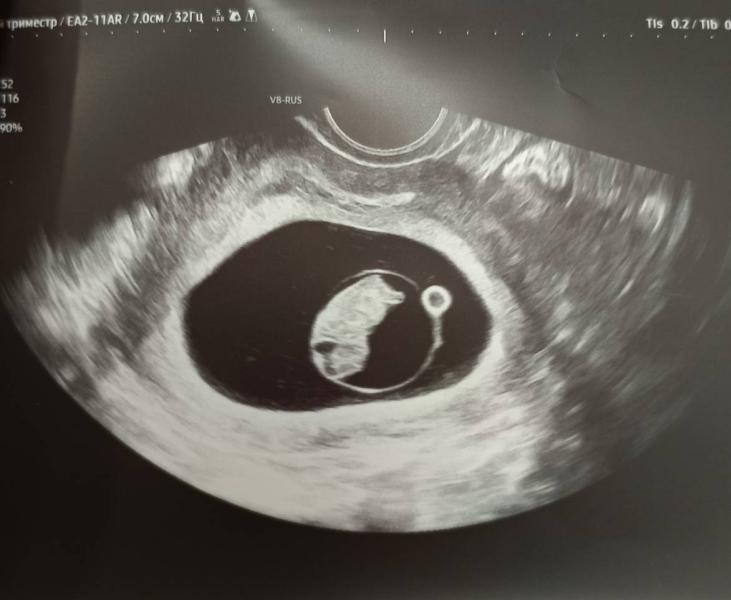

Такой вопрос, сегодня была на УЗИ. Нашли гематому 25 мм* 7,5 мм, кроме легкого потягивания живота ничего не беспокоит ттт, у кого было и что делали?

У меня тоже выявили гематому на УЗИ на 10 неделе, выделений не было, низ живота немного тянул. Меня положили на неделю в больницу, выписали также с гематомой. На 13 неделе пошла на первый скрининг , гематома на месте… сказали должна пройти через месяц где то, вот жду второй скрининг надеюсь пройдет

У меня 11мм на 6мм по моему.